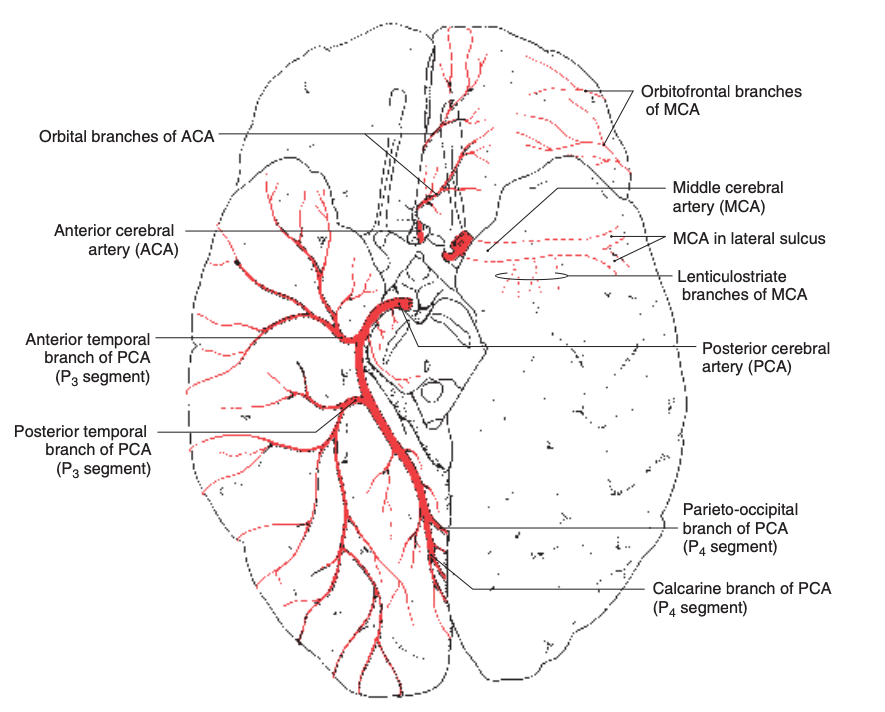

Anatomie des branches périphériques :

Source : Neuroanatomy: An Atlas of Structures, Sections, and Systems, 8th Edition, Duane E. Haines